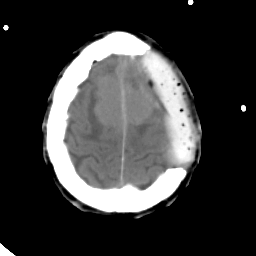

Meningioma: Roentgen-ray CT #2 -- Slice #18

[Home][Help][Clinical] Slice 18